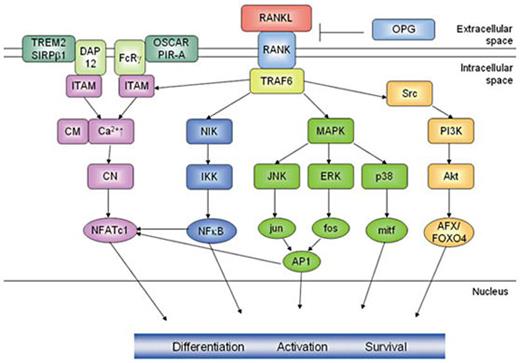

The RANK signaling cascade (fig. 1) is initiated when RANKL binds to the extracellular domain of RANK which passes the signal along to TRAF6 (TNF receptor-associated factor 6) [133,134,135,136,137,138]. By transfecting RANK deficient cells in RANK mutants that are incapable of binding either TRAF 1, 2, 3, 5, or 6 Armstrong et al.[ 134] were able to demonstrate that predominantly TRAF6 was essential for the induction of osteoclastogenesis. TRAF6 has various downstream mediators which control the expression of osteoclast-specific genes during differentiation and activation of osteoclasts. The two most investigated pathways are the activation of the transcription factors NF-ĸB and AP-1 (activated protein 1). Targeted disruptions of the p50/p52 component of NF-ĸB and the c-fos component of AP-1 resulted in impaired osteoclastogenesis and revealed an osteopetrotic phenotype [139,140,141]. AP-1 is activated by signaling cascades mediated by JNK (c-Jun N-terminal kinase) whereas the phosphorylation of the inhibitor of NF-ĸB kinase (IKK) leads to the activation of NF-ĸB [142,143,144,145,146,147]. Other cascades of mitogen-activated protein kinases such as the TGF-β-inducible kinase TAK1 and the p38 stress kinase have also been described to participate in RANK signal transduction [148,149,150]. p38 is activated via the phosphorylation by MKK6 and in turn activates the transcriptional regulator mi/Mitf, which is responsible for the transcriptional control of genes encoding for the osteoclast-specific enzymes TRAP and cathepsin K [151, 152]. ERK (extracellular signal-related kinase) is a downstream target of MEK1 and acts as a negative regulator of osteoclastogenesis for ERK inhibitors have shown to accelerate RANKL-induced osteoclastogenesis [153]. The serine/threonine kinase Akt and the phosphatidylinositol-3-OH kinase (PI(3)K) are downstream elements of src and are known to mediate cell survival, motility and cytoskeletal rearrangements by the activation of the MEK/ERK and Akt/NFĸB pathways [121,154]. Recently, AFX/FOXO4 was shown to be the key downstream mediator activated by Akt/PKB to modulate osteoclast survival [155].

RANK signaling in osteoclasts. The RANK signaling cascade is initiated upon the binding of RANKL to the extracellular domain of RANK which passes the signal along to TRAF6. The activation of TRAF6 initiates pathways leading to the activation of the transcription factors NFAT, NFkB, the MAP kinase mediators jun, fos and p38 as well as the down-stream targets of Akt AFX/FOXO4, which contribute to osteoclast differentiation, activation and survival. The ITAM-containing co-stimulatory molecules DAP12 and FcRγ, respectively, initiate Ca2+-signaling leading to the activation of NFATc1. This schematic representation only focuses on the most important pathways, not illuminating further interactions of the signaling mediators.

RANK signaling in osteoclasts. The RANK signaling cascade is initiated upon the binding of RANKL to the extracellular domain of RANK which passes the signal along to TRAF6. The activation of TRAF6 initiates pathways leading to the activation of the transcription factors NFAT, NFkB, the MAP kinase mediators jun, fos and p38 as well as the down-stream targets of Akt AFX/FOXO4, which contribute to osteoclast differentiation, activation and survival. The ITAM-containing co-stimulatory molecules DAP12 and FcRγ, respectively, initiate Ca2+-signaling leading to the activation of NFATc1. This schematic representation only focuses on the most important pathways, not illuminating further interactions of the signaling mediators.

However, on the level of transcription factors nuclear factor of activated T cells c1 (NFATc1) has been elected as the master regulator of osteoclastogenesis. Many downstream effectors of RANK such as NF-ĸB and AP-1 contribute to the activation of NFATc1. Furthermore, RANKL-induced Ca2+-signaling, mediated by immunoreceptor tyrosine-based activation motifs (ITAMs), has been shown to be indispensable for osteoclastogenesis, since mice deficient in the ITAM-containing adaptor molecules DAP (DNAX-activating protein) 12 and Fc common receptor γ chain (FcRγ) are severely osteopetrotic. After retroviral transfer of DAP12 the osteopetrotic phenotype was rescued. The association of paired immunoglobulin-like receptor A (PIR-A) and OSCAR to FcRγ and triggering receptor expressed on myeloid cells (TREM) 2 and signal-regulatory protein β1 (SIRPβ1) to DAP12 in osteoclast precursors is considered to act as a co-stimulatory signal for RANKL, since one signal by its own is not able to induce osteoclastogenesis [156,157,158].